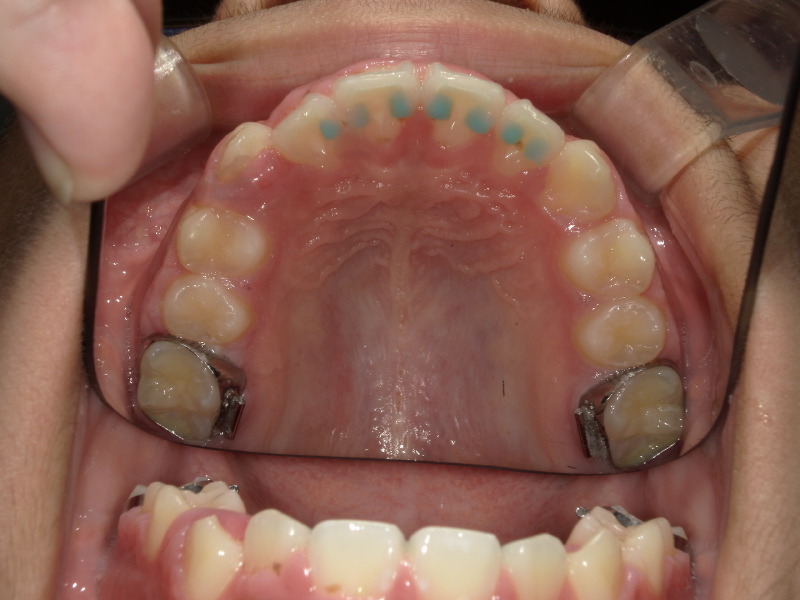

BWSの装着

アクティビティーも順調に進み、次は八重歯の歯を綺麗に入れるために装置を併用することになりました。

装置装着日 3ヶ月後

少しずつ入れる余裕が出てきています。

この間もマウスピース、アクティビティーは継続しています。

一時的に顎の中に装置が入りますが上顎なのでそこまで見えたり気になることはないです。